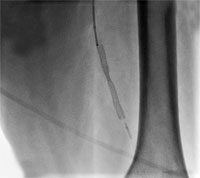

Рис.2. Дооперационная ангиография. Стеноз левой поверхностной бедренной артерии в среднем сегменте до 80%.